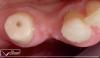

Фото 1. Пациент обратился за помощью в 2009 с адентией в области 31 зуба.

Фото 2. В 2016 году у пациента не отмечалось изменения позиции 1 зуба.

Фото 3. 18 зуб пациента пришлось удалить из-за трещины.

Фото 4. Признаки экструзии 15 зуба в 2016 году.